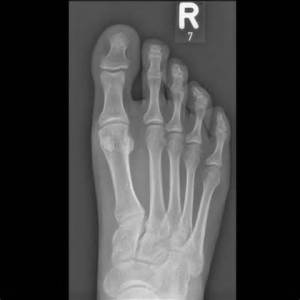

After about 20 minutes (and a few games of Candy Crush Saga) I got called into the back room to recite my entire health history and to get a few X-rays of my starboard side tootsie. Say cheese!

His initial words: “I want to check first for signs of a stress fracture.”

“Nope, it looks good.”

So after Dr. Wang did some bending and poking (of my feet, you perverts) the prognosis was actually quite good.